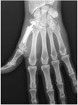

Le diagnostic repose sur la clinique. Les radiographies de face et de profil de l’articulation trapézo-métacarpienne (T-M) sont nécessaires pour confirmer le diagnostic, établir le stade de l’arthrose et dans certains cas faire le diagnostic différentiel avec l’arthrose péritrapézienne qui peut toucher toutes les surfaces articulaires du trapèze.